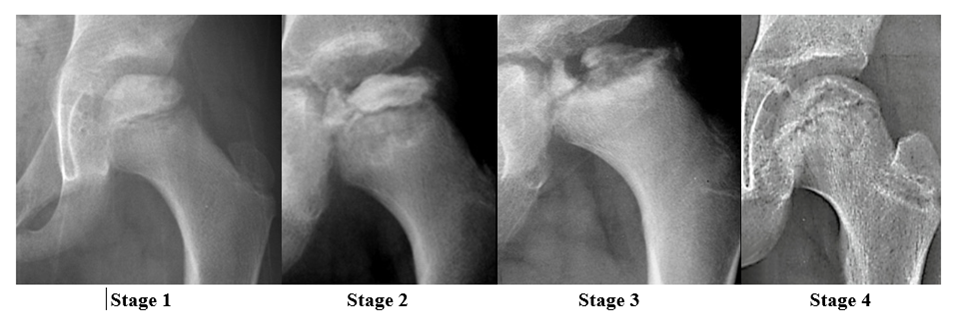

There are several classifications systems used to classify the stages of LCPD; however, this paper will use the Waldentrom classification, which refers to the associated radiographic findings for each stage. The initial stage (stage 1) results from infarction, which produces a smaller and sclerotic epiphysis with medial joint space widening. This stage may be radiographically occult for 3-6 months. The fragmentation stage (stage 2) typically begins with a subchondral lucent line (crescent sign) and then progresses to fragmentation and resorption of bone, resulting in femoral head collapse and patchy sclerotic density. The re-ossification stage (stage 3) occurs as the ossific nucleus undergoes re-ossification in which the necrotic bone is resorbed and new bone replaces. The healing or remodeling stage (stage 4) consists of femoral head remodeling until skeletal maturity. Once fully healed, the remodeled hip has the classic coxa plana, coxa magna, and “sagging rope sign” radiographic features. Dependent upon proper treatment and other patient variables, the degree of resultant deformity will vary amongst patients.